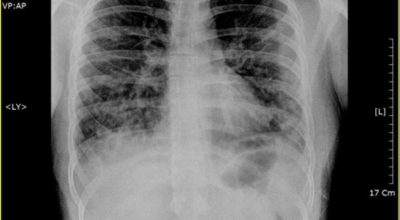

건강한 폐를 위해서는 폐의 활동을 유지하는데 도움을 주는 건강에 좋은 음식을 섭취해야 합니다. 폐는 우리 몸에서 중요한 역할을 하는 것은 말할 필요도 없어요. 그러나 결국 폐는 공기 뿐만 아니라 대기 오염과 담배 연기 같은 유해한 요소를 흡입하게 되는데요. 이런 오염 물질은 천식, 기관지염, 낭포성 섬유증 또는 폐렴등의 호흡기 건강 문제의 위험을 증가시켜요.

세계보건기구인 WHO 에 의하면 2억 3천5백만 명이 천식으로 고통 받고 있으며 이는 진단 또는 치료가 부족한 상태이지요. 그렇기 때문에 폐 건강을 향상시키기 위해서는 폐에 좋은 음식을 섭취할 필요가 있어요.